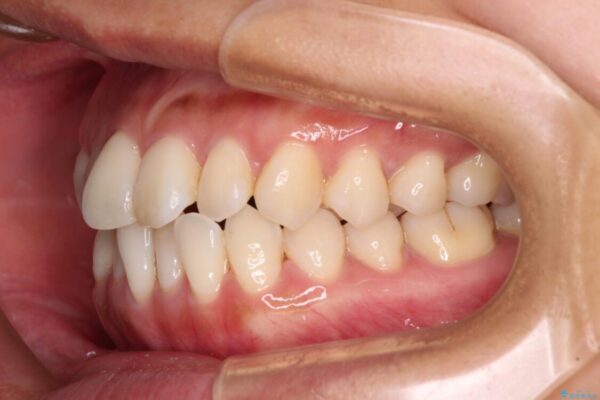

前歯のデコボコで前方に出ていることを気にして来院された患者様です。

上顎前歯が捻れて前方に飛び出しており、下顎前歯もそれに沿うようにデコボコとなっていました。

IPR(歯と歯の間を削る処置)によりスペースを獲得して上下顎前歯のデコボコを改善し、飛び出している前歯が引っ込むように設定し、インビザラインにて矯正治療を行うこととしました。

治療前

• 【モニター】前歯のデコボコをインビザラインで改善 治療前画像